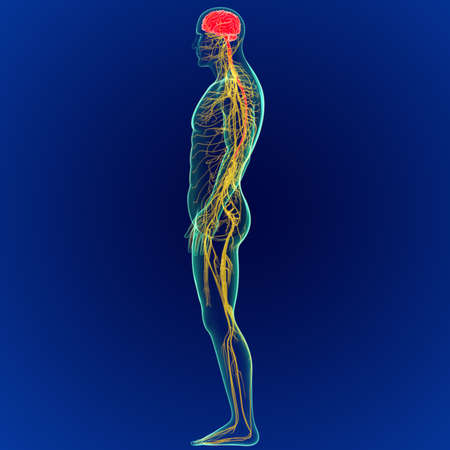

3D Illustration Concept of Central Organ of Human Nervous System Brain Anatomy

Illustrating the role of the central nervous system in processing sensory information and coordinating motor responses.

A captivating digital depiction of the human nervous system, highlighting the brain and spinal cord with glowing neural connections, perfect for educational materials.

Detailed anatomical illustration showing the human brain, spine, and nervous system with a focus on the intricate connections between them

An Electro stimulation digital illustration of human nervous system, highlighting brain and spinal cord with glowing nerve pathways

Vivid visualization of the human nervous system, highlighting brain and spine against dark blue background